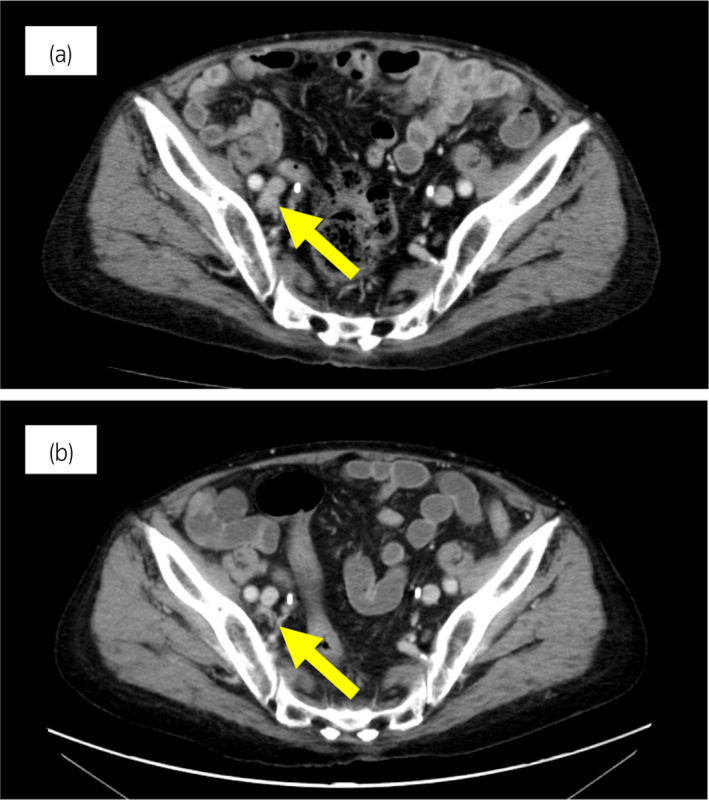

一名 78 歲男性被診斷為 cT3bN0M0,GS 為 4 + 4 =⟩8,PSA 水平為 15.2 ng/ml 7 年前,并接受了前列腺切除術(shù)。 六個(gè)月后,PSA 升高并開(kāi)始雄激素剝奪治療。 兩年后,開(kāi)始使用比卡魯胺治療 CRPC。 服用比卡魯胺五個(gè)月后,患者被轉(zhuǎn)診至佳學(xué)基因檢測(cè)合作醫(yī)院。 在接下來(lái)的 2 年內(nèi),依次給予恩雜魯胺、多西他賽和卡巴他賽。 多西他賽前的 MRI 顯示髂骨轉(zhuǎn)移,多西他賽和卡巴他賽治療后消失。 開(kāi)始使用卡巴他賽后 6 個(gè)月,他出現(xiàn)雙側(cè)盆腔淋巴結(jié)腫大,并在膀胱后壁發(fā)現(xiàn)轉(zhuǎn)移性腫瘤。 在進(jìn)行經(jīng)尿道切除術(shù) (TUR) 期間,從膀胱中的轉(zhuǎn)移性腫瘤獲得組織樣本。 病理檢查顯示嗜鉻粒蛋白 A 陽(yáng)性,NSE 水平升高,因此我們?cè)\斷為 NEPC。 卡鉑和依托泊苷聯(lián)合治療縮小了腫瘤。 此后,在 24 個(gè)月內(nèi)進(jìn)行了 17 個(gè)療程,疾病得到控制。 由于神經(jīng)病變和疲勞而停止化療。 隨后,患者出現(xiàn)盆腔淋巴結(jié)轉(zhuǎn)移進(jìn)展(圖 4a)。 通過(guò)血液檢測(cè) (BRCAnalysis®?) 進(jìn)行的基因檢測(cè)對(duì) BRCA 突變呈陰性。 使用 TUR 時(shí)收集的膀胱轉(zhuǎn)移組織進(jìn)行腫瘤正確用藥850基因檢測(cè)。 結(jié)果顯示,該患者的體細(xì)胞 BRCA2 突變呈陽(yáng)性。 在奧拉帕尼給藥后的 3 個(gè)月內(nèi),淋巴結(jié)從 21.0mm 縮小到 7.5mm(圖 4b)。 PSA 從 1.42 下降到 0.07 ng/ml,NSE 從 22.3 下降到 11.8 ng/ml。

圖 4:病例 2:奧拉帕尼治療前和治療后 3 個(gè)月的盆腔淋巴結(jié) CT 圖像。 (a) 治療前和 (b) 奧拉帕尼治療后 3 個(gè)月。 黃色箭頭顯示轉(zhuǎn)移淋巴結(jié)。